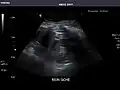

Aorta: Visualized portions normal in caliber, 16 x 15 mm.

Aorta